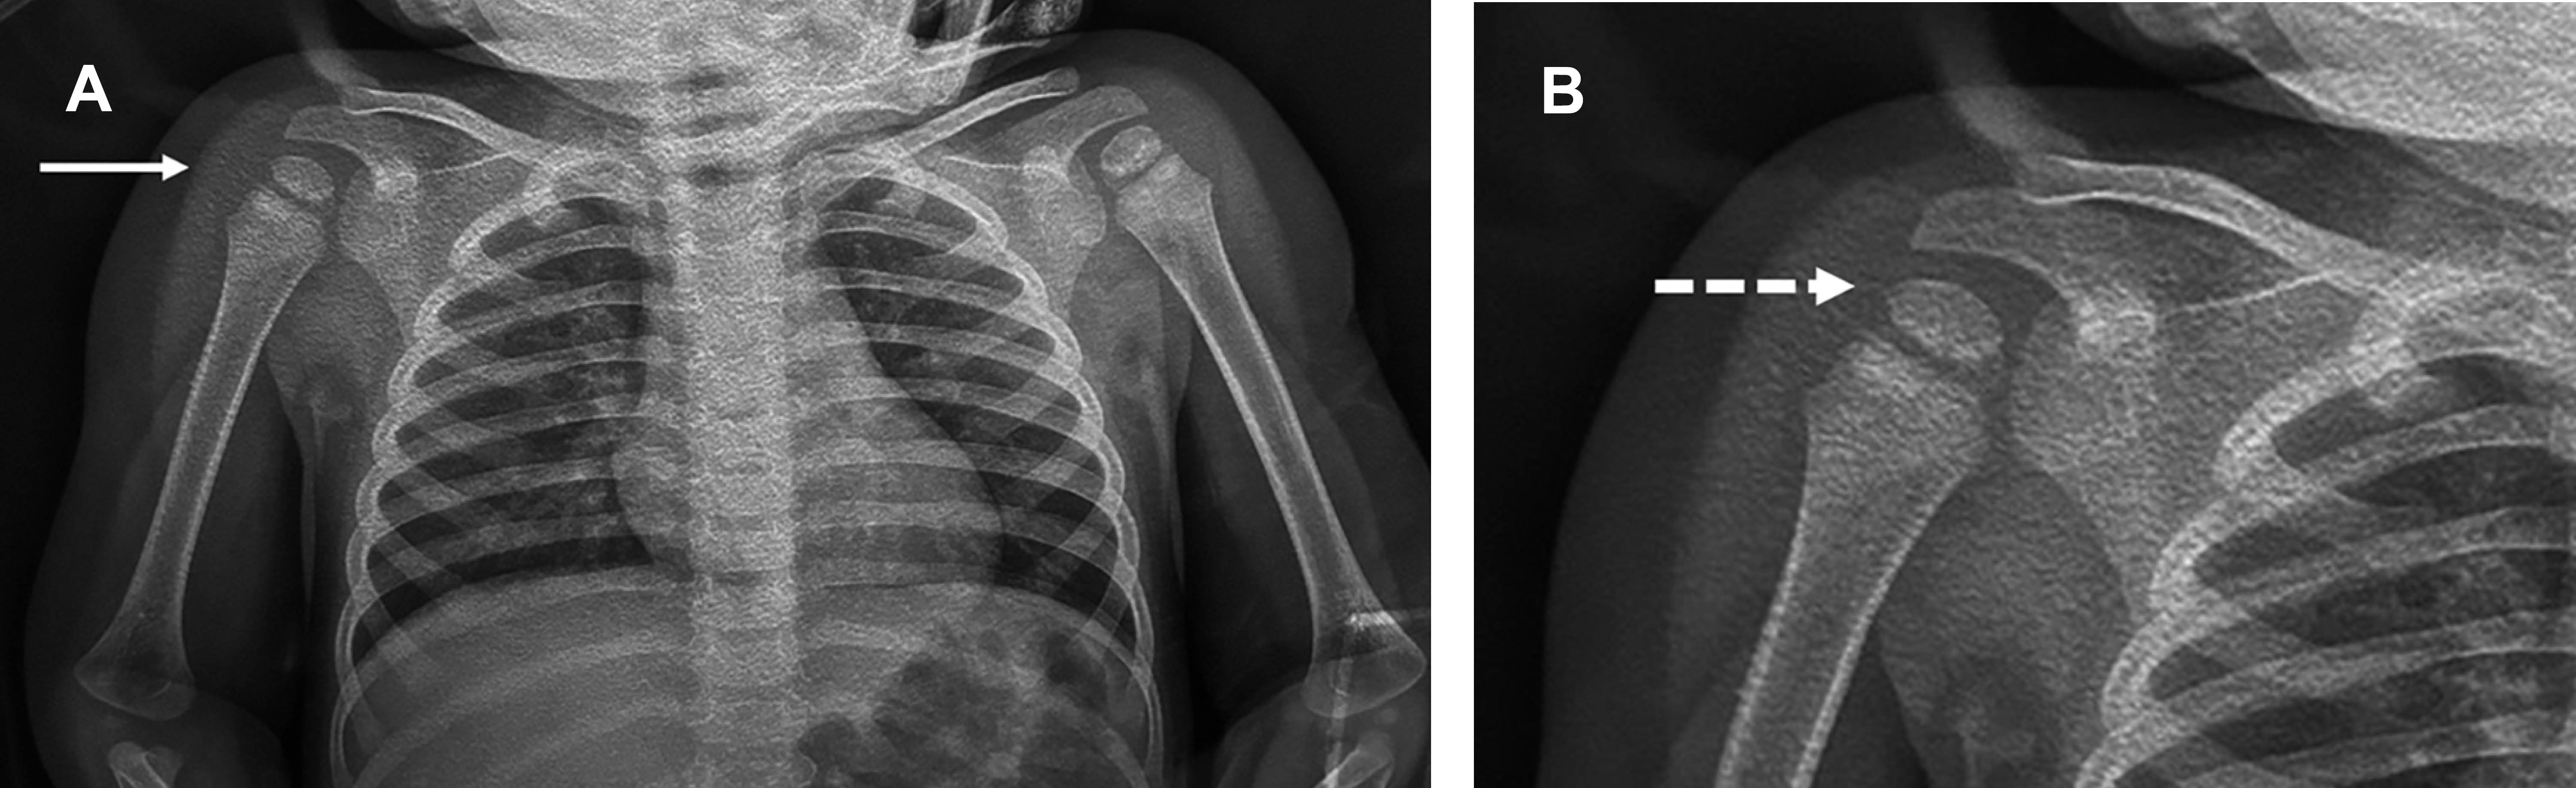

Femenino lactante mayor de 18 meses, con antecedentes perinatales sin problemas, quien dos horas antes presentó caída de su cuna, la madre la encontró en el suelo, con llanto y negativa a mover hombro derecho. A la exploración dirigida, se encontró: pérdida del contorno normal del deltoides, cabeza humeral derecha desplazada anteriormente y dolorosa al compararla con la contralateral, con imposibilidad pasiva y activa y para realizar flexión de hombro; clavícula, codo, antebrazo y mano normales, al igual que examen neurológico y llenado capilar. Con diagnóstico de luxación anterior de hombro derecho vs fractura humeral, se efectuó radiografía con la que se confirmó la luxación glenohumeral anterior (Figura 1); bajo sedación se efectuó reducción cerrada, la radiografía de control corroboró la reducción (Figura 2), se inmovilizó el miembro superior derecho con vendaje tipo Desault.

Figura 2